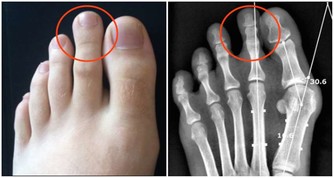

因而角膜會逐漸變尖,最終形成圓錐角膜,圓錐角膜的後果是使視力永遠喪失。

實行了LASIK後所產生的圓錐角膜目前在醫學上被認為是絕症,最後只能用角膜移植來解決問題!